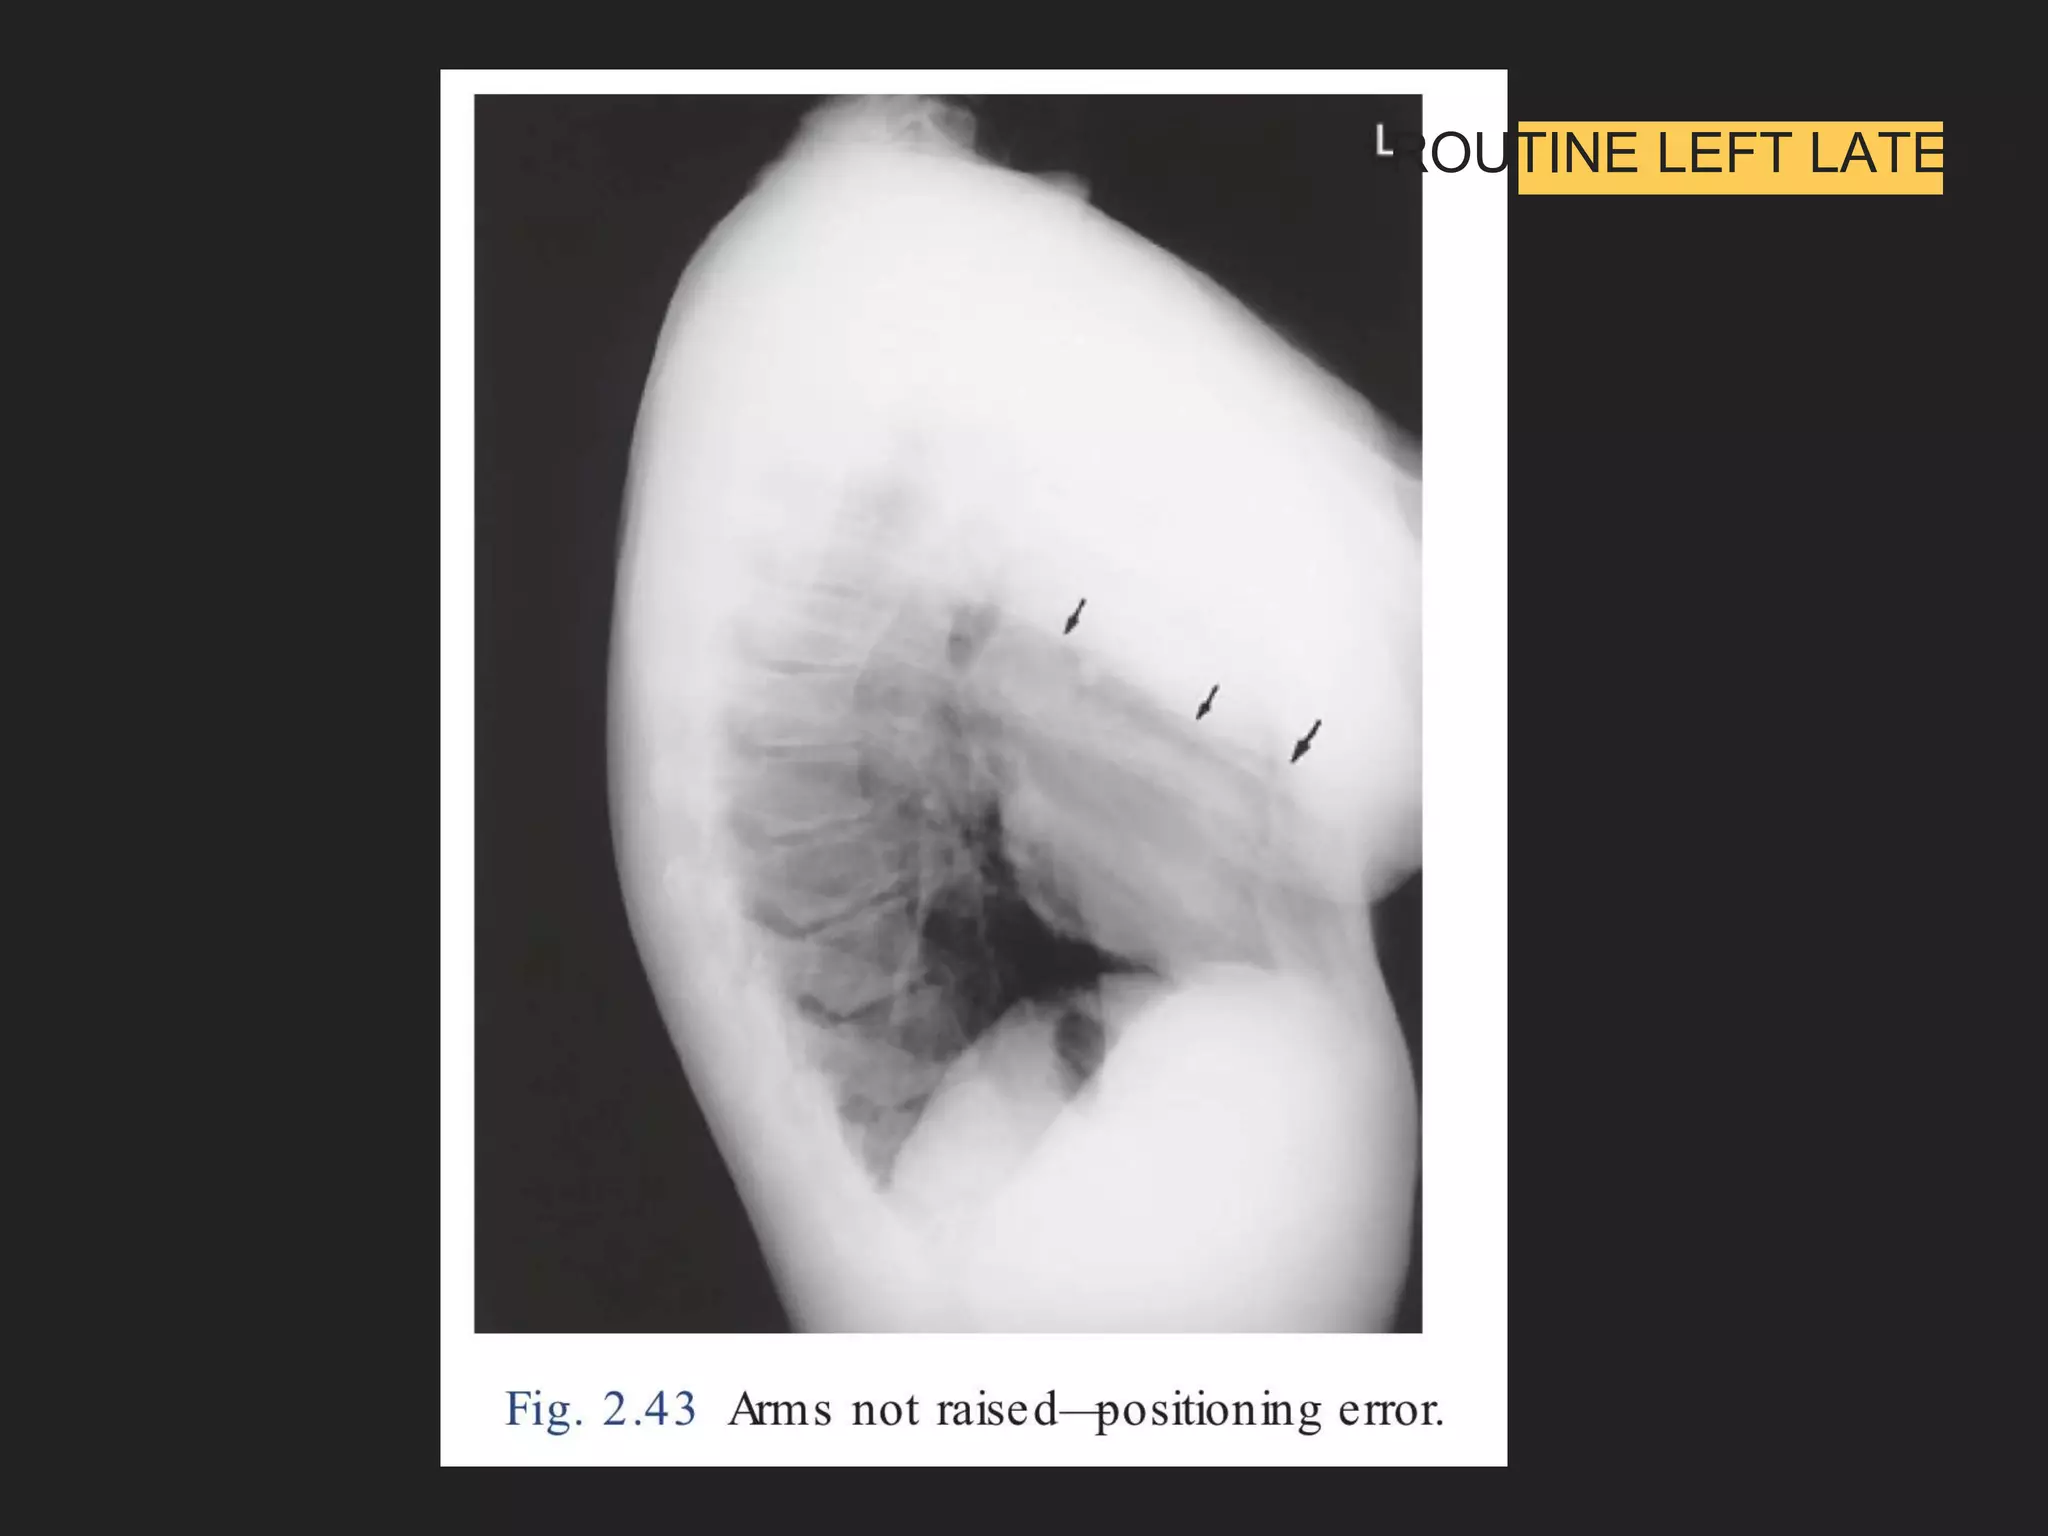

The document provides detailed instructions for performing a chest x-ray, emphasizing proper patient positioning and technical requirements for optimal image quality. Key points include centering the trachea, ensuring full inspiration, and visibility of specific anatomical features. Additionally, it outlines collimation margins and patient stance to achieve a clear view of lung fields.